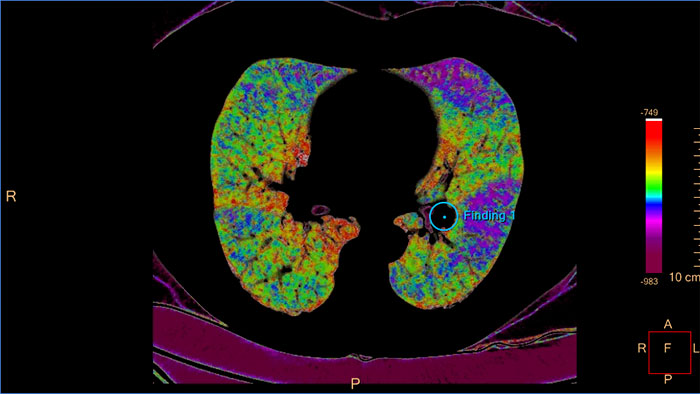

Aplikacja kliniczna umożliwia wizualizację i analizę ilościową destruktywnego procesu choroby śródmiąższowej płuc (np. rozedmy płuc). Wspomaga ona pracę użytkownika, przeprowadzając go przez procesy analizy dróg oddechowych, przeglądu i pomiaru wielkości światła dróg oddechowych oraz oceny zaklinowanego powietrza.

Aplikacja CT COPD służy do ilościowej obserwacji destruktywnego procesu choroby śródmiąższowej płuc (rozedmy płuc) oraz lokalizacji obszarów płuca objętych chorobą.